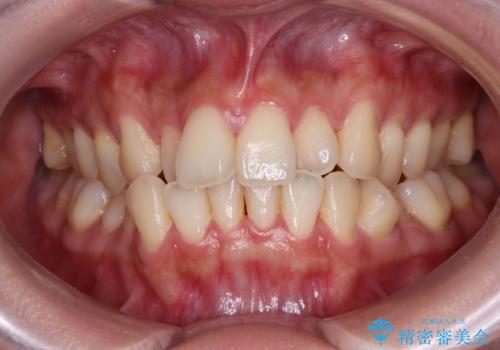

八重歯と重なった前歯 目立たない装置での抜歯矯正

担当医 藤巻太一朗